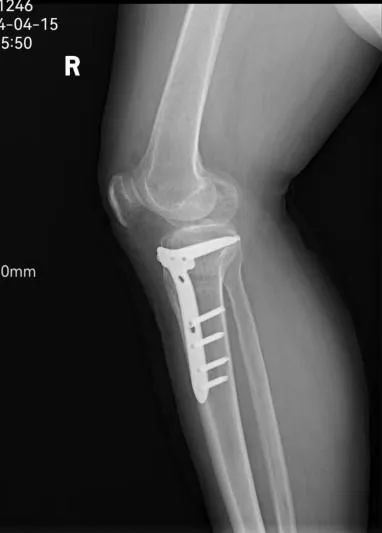

45岁的患者牛某,因5年前外伤致右胫骨平台骨折,未行手术治疗,伤后半年开始负重行走,致使右膝关节不稳定,且逐年加重。患者因右膝关节不稳定,不敢快速行走及下台阶,且摔倒数次,产生了恐惧心理。辗转多家医院后,均疗效不明显。 听闻“京长合作”首都医科大学附属北京积水潭医院每月定期派专家来长治二院骨科坐诊、查房、手术的医讯,主动要求北京积水潭专家手术治疗,近日来我院就诊要求住院手术治疗。 门诊经查体及阅读各项检查后以“右胫骨平台骨折畸形愈合”便收住院。 入院诊断: 1.右胫骨平台骨折畸形愈合 2.高血压病 住院期间,北京积水潭医院骨科吴宏华副主任医师结合查体及辅助检查,考虑患者畸形为关节外畸形,下肢力线向前内侧偏移,建议行胫骨内侧高位双平面截骨纠正对位及力线。考虑开放行双平面截骨,创伤较大,建议3D打印HTO截骨导板,在导报引导下行微创双平面截骨。在全身麻醉下在截骨导板引导下行截骨矫形术。 术后3天患者牛某持助行器下地行走,右膝关节不稳定感觉消失,恐惧心理消失,心情舒畅,对手术效果非常满意。 此次手术是在北京积水潭吴宏华副主任医师指导下,长治二院首次将HTO截骨技术应用于创伤骨科,是“京长合作”带给长治二院骨科发展的新动力,更为我市骨病患者带来的福音。 科室推荐 创伤骨科二病区隶属于长治二院骨科创伤专业,成立于 1978年建院之初,至今已历时 40 余年。创伤二病区现有开放床位 35 张,共有医师 10名(含返聘医师),护士 9 名。其中主任医师 1名,副主任医师 1 名、主治医师 6名、住院医师 2 名。 病区主任:李黎明,主任医师、长治市工伤医疗鉴定专家、北医三院进修学员,擅长复杂骨折的手术修复,尤其在骨盆骨折、关节周围骨折的手术治疗方面技术精湛。 创伤二病区诊疗疾病范围:肩胛骨骨折、肩(胸)锁关节脱位、锁骨骨折、肱骨近段骨折、肱骨干骨折、肱骨髁骨折、尺骨鹰嘴(冠突)骨折、尺桡骨骨折、桡骨远端骨折、各类型骨盆骨折、髋臼骨折、股骨头骨折、股骨颈骨折、股骨粗隆间骨折、股骨干骨折、股骨髁骨折、髌骨骨折、胫骨平台骨折、胫腓骨骨折、各类型踝关节骨折(韧带损伤)、各类型开放(闭合)性软组织损伤、陈旧性骨折不愈合、骨感染(骨髓炎)、内固定周围骨折、骨折非手术治疗、骨折康复指导等。 咨询热线 0355—3126025 主任医师 创伤骨科二病区主任 擅长复杂四肢骨折、骨盆骨折,脊柱骨折、颈椎病、腰椎管狭窄等的诊治。在肢体复杂损伤、脊柱退变疾病方面有较多深入研究。多次在北京、太原等省内外三甲医院进修学习,具有丰富的理论知识。 【学术任职】 长治医学院副教授、长治市骨科专业委员会委员、长治市足踝外科委员会委员、长治市医疗专家库成员,长治市工伤、司法鉴定专家组成员。在国家级省级专业杂志发表论文学术论文10余篇,在专业学术领域积累了丰富的临床经验。 医生推荐 徐彦芳 副主任医师 骨科学硕士 北京大学国内访问学者 【专业特长】 【学术任职】 咨询热线 李黎明主任 13097569000 徐彦芳医生 15635598825 供 稿丨徐彦芳 编 辑丨卞 晨 审 核丨雷 赫